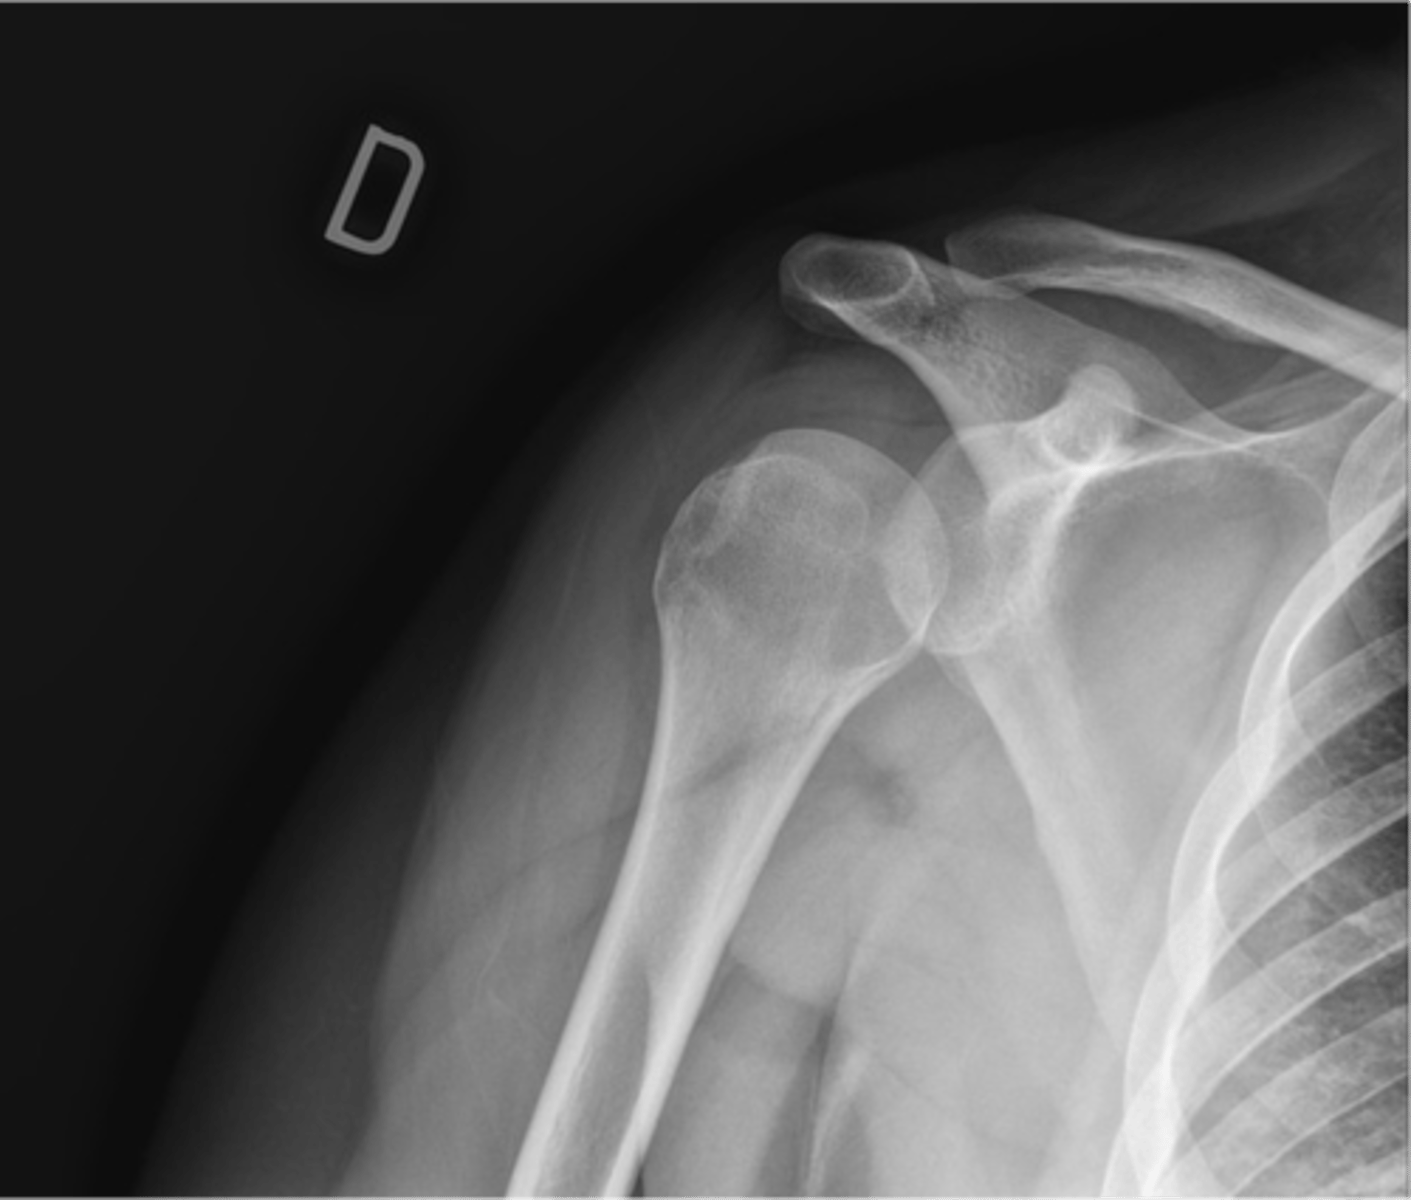

TRUE!!--we see healthy space b/w the clavicle and acromion, the humerus and the acromion, and b/w the glenoid and humerus...also, there is no sclerosing or osteophytes

True or false: this is a healthy GHJ

1. Distal clavicle

2. Coracoid

3. Glenoid

4. Head of humerus

5. Lesser tuberosity

6. Greater tuberosity

7. Clavicle

8. AC joint

Label this image.

INTERNAL, because the lesser tuberosity is positioned medially vs. in line with the greater tuberosity, as seen in external rotation

Is this shoulder in EXTERNAL or INTERNAL rotation? Why?